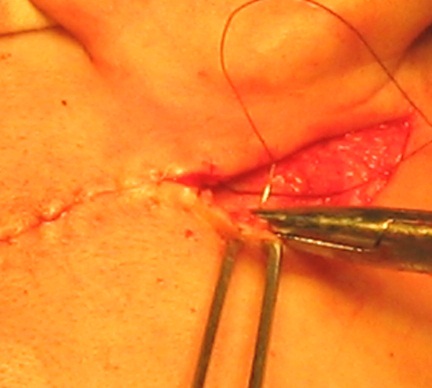

Miután az implantátum csonthártya lebeny van rögzítve a helyén varratokat a széle a műszerfal és a csonthártya. lágyszövet metszést összevarrtuk rétegekben. bőr varrás lehet twining kerek, csomópont, intradermális. (6. ábra)

6. ábra - Layered sebvarró, varrat